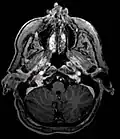

_in_a_patient_with_VHL.jpg) Ectopic functional paraganglioma (glomus jugulare) in a patient with VHL. T2 weighted MRI at the same location demonstrates a high signal mass consistent with a paraganglioma. Extra adrenal paragangliomas can be found in VHL (arrow). Ectopic functional paraganglioma (glomus jugulare) in a patient with VHL. T2 weighted MRI at the same location demonstrates a high signal mass consistent with a paraganglioma. Extra adrenal paragangliomas can be found in VHL (arrow).